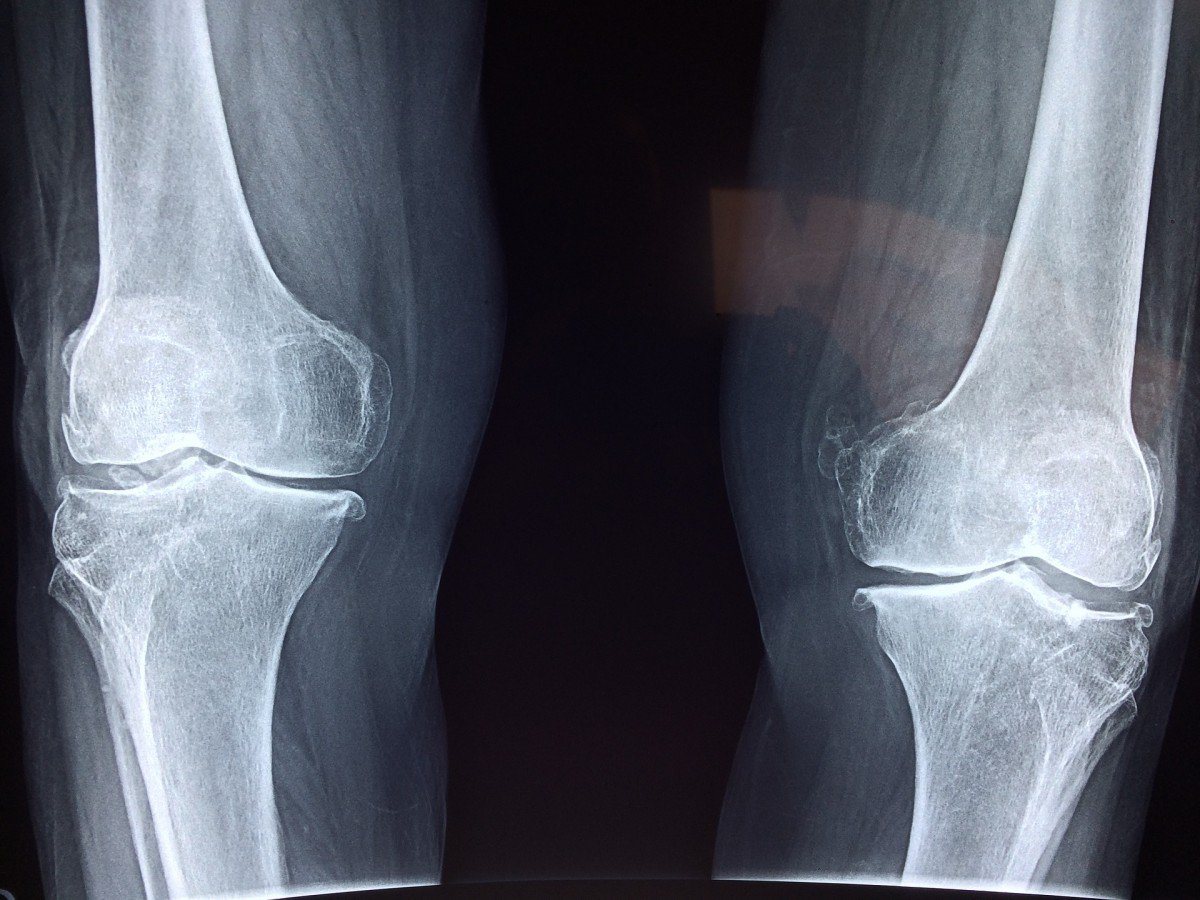

Botten zijn een fascinerend voorbeeld van het regeneratievermogen van het lichaam. Ze kunnen weer volledig functioneren – zelfs na een breuk – dankzij hun vermogen om nieuw, veerkrachtig weefsel te vormen op de plaats van de breuk. “Wanneer het echter gaat om gecompliceerde breuken of groot weefselverlies, is zelfs het zelfherstellend vermogen van een bot onvoldoende”, legt professor Thomas Groth uit, hoofd van de onderzoeksgroep Biomedische Materialen aan het Instituut voor Farmacie van de MLU. Dan moeten implantaten uitkomst bieden. Dat gaat echter niet altijd goed.